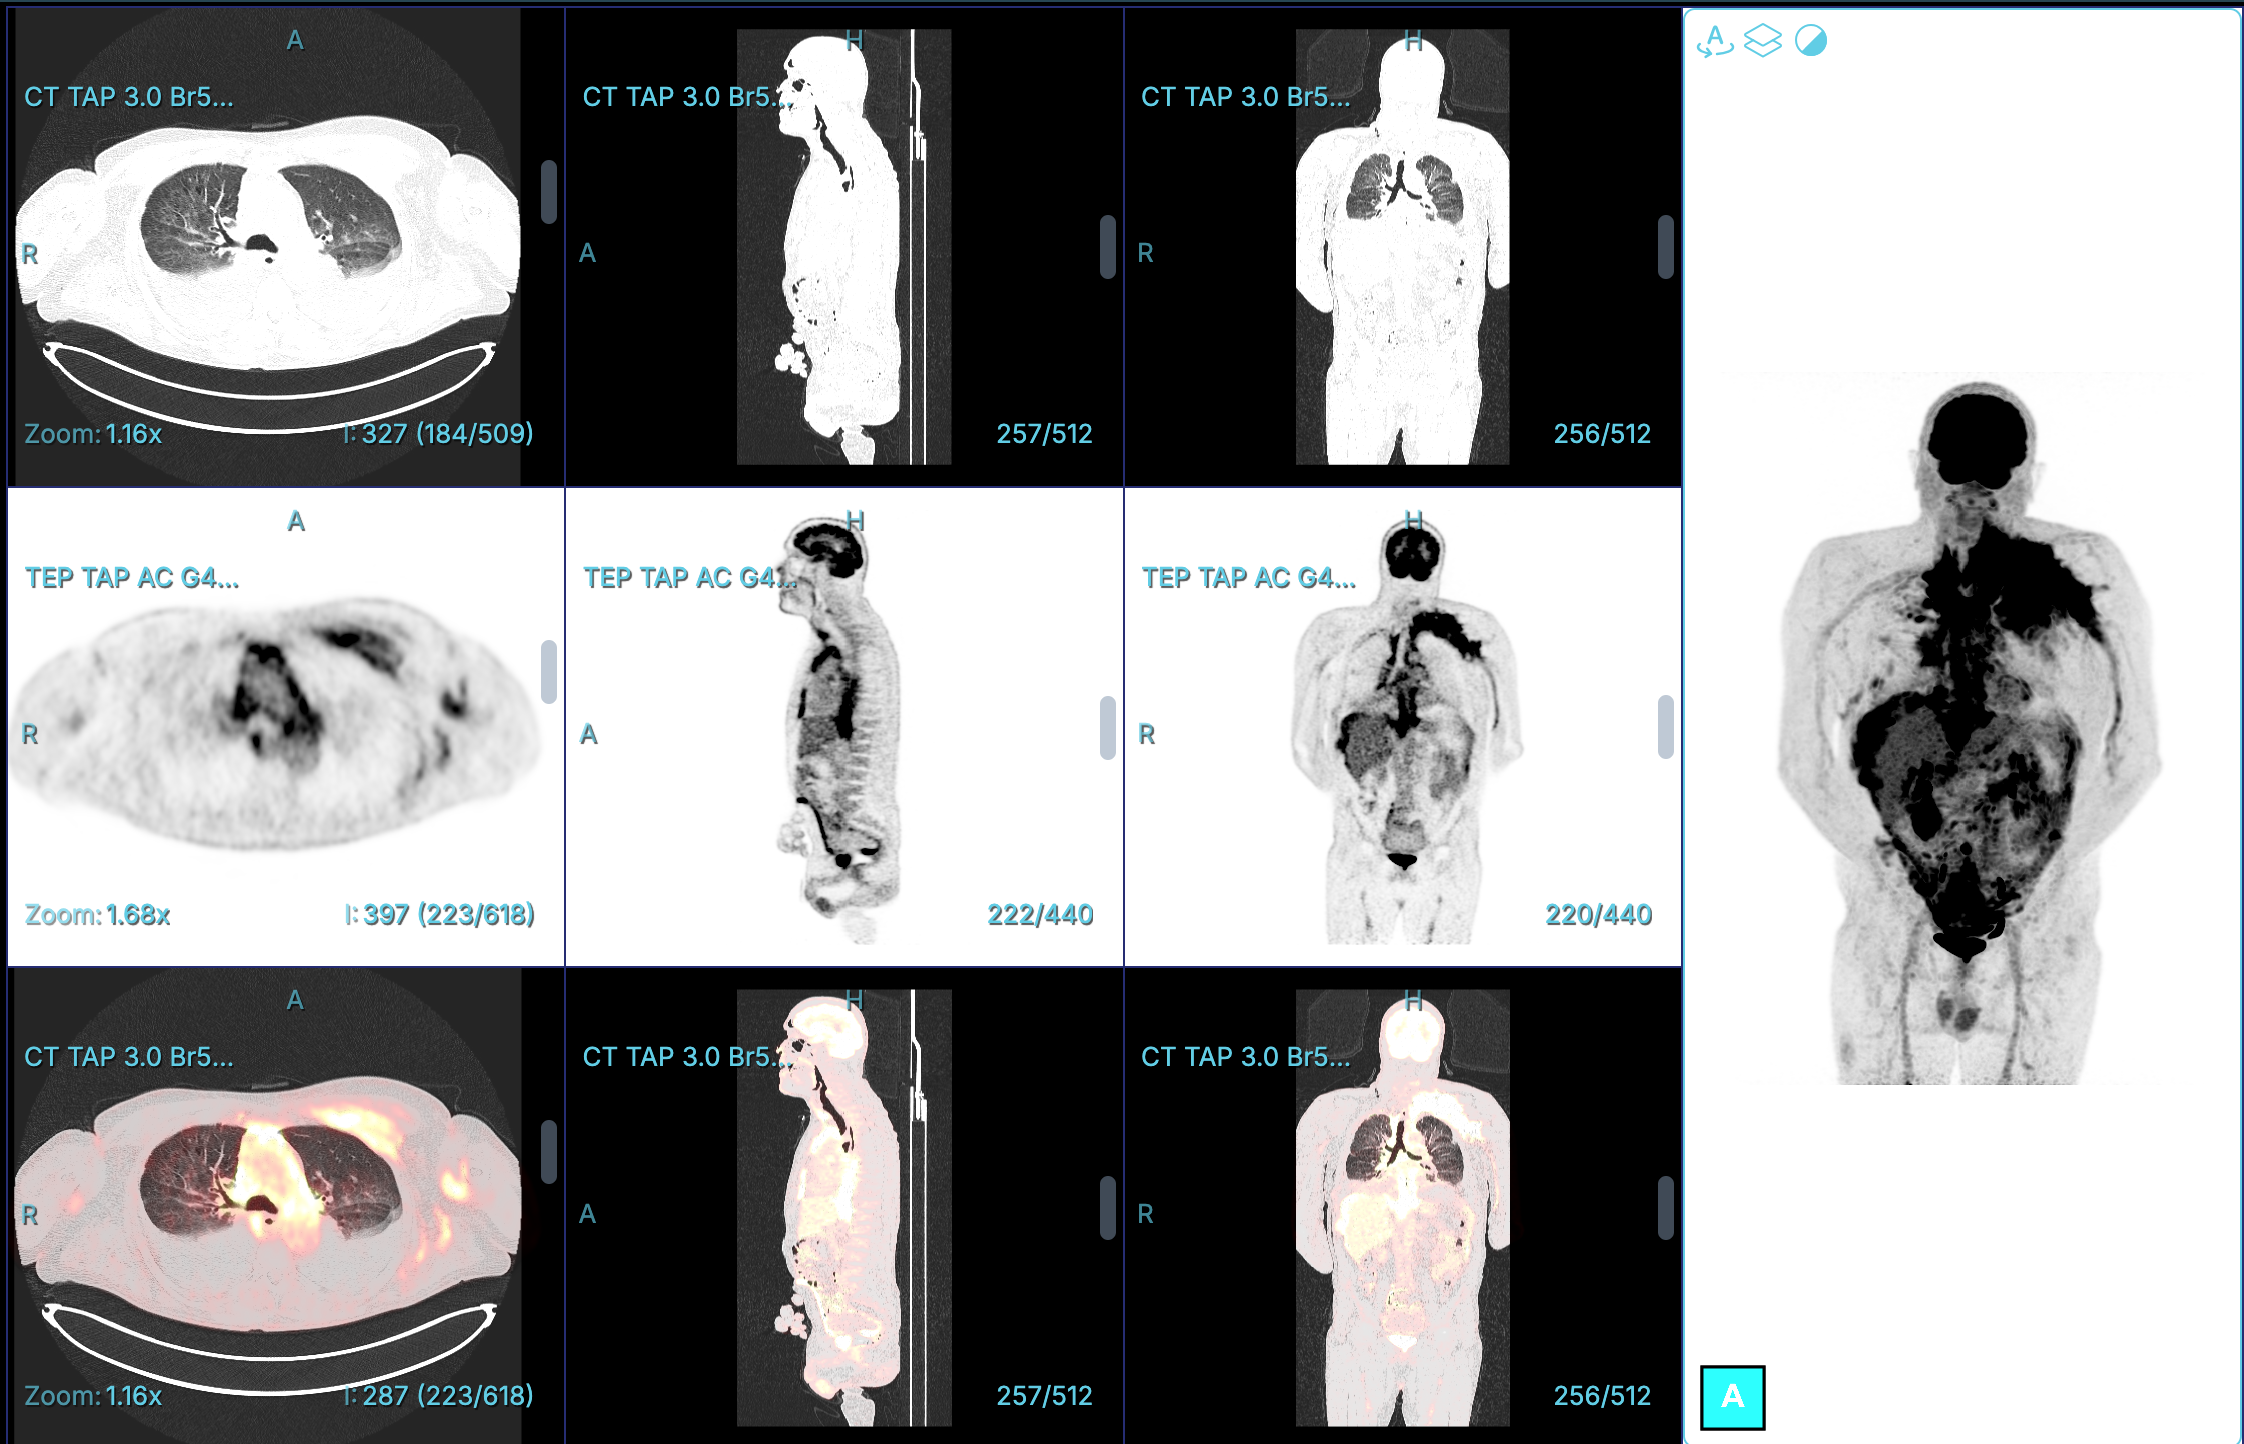

Patient suivi pour une pathologie de type X. La TEP-TDM met en évidence une fixation intense au niveau d’un épaississement pleural diffus, s’étendant de manière diffuse dans le médiastin ainsi que dans le péricarde. Une infiltration péritonéale est également présente.

Le diagnostic à évoquer est un Mésotheliome pleural , l’atteinte pleural reste assez typique.

Épaississement pleural diffus ou nodulaire avec captation intense du 18-FDG.

Effet de masse sur le poumon adjacent, parfois avec collapsus partiel.

Extension pariétale possible (muscles intercostaux, côtes, diaphragme).

Adénopathies médiastinales ou hilaires hypermétaboliques.